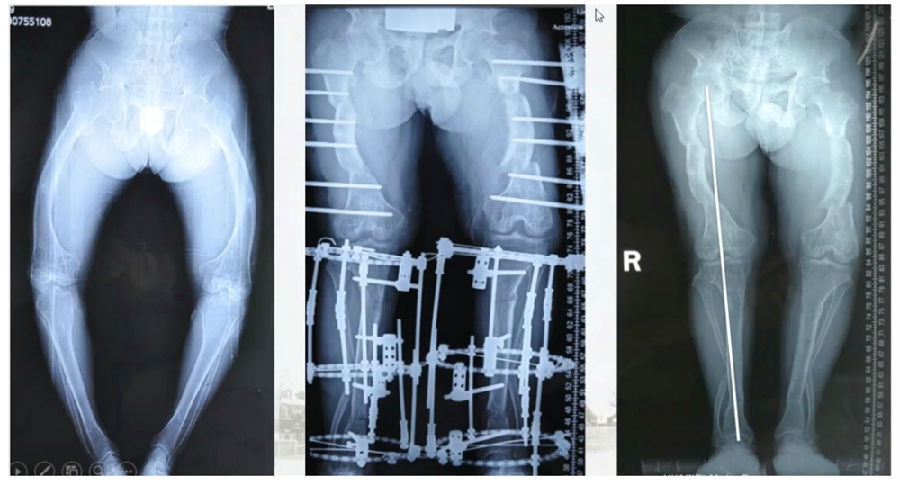

典型病例,男性,65岁,农民,双膝内翻16度。

术前影像

第一次为该患者做了传统上行开放截骨,撑开角度较大,术后用三种方法测量髌骨高度,发现髌骨高度受到影响,髌骨变低了。

左膝上行OWHTO(初次)

上行OWHTO髌骨高度测量

ISI法测量髌骨无明显变化;CDIBPI法测量髌骨降低明显;患者屈膝锻炼困难。

第二次来院做另一侧肢体时,采用下行截骨,术后患者髌骨高度,无论用哪种方法测量都无明显变化,而且患者膝关节功能迅速得到恢复。

右膝下行OWHTO(再次)

下行OWHTO髌骨高度测量

ISI法测量髌骨无明显变化;CDIBPI法测量髌骨无明显变化;患者屈膝明显改善。